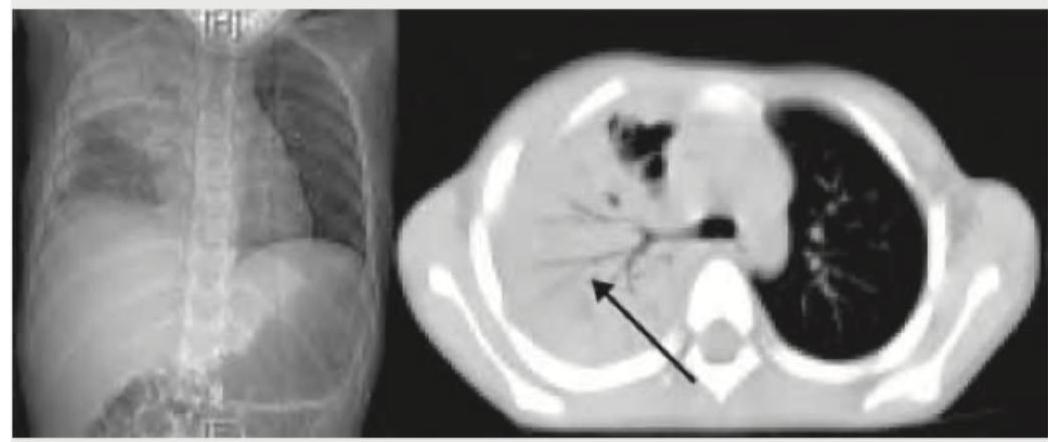

What does this CT chest image show?

Explanation: ***Segmental collapse*** - The CT image shows loss of lung volume in a specific segment, indicated by the **crowding of bronchi and vessels in the affected area**, which is suggestive of atelectasis or collapse. - The black arrow points to the collapsed segment, which appears as a **densified, airless region within the lung parenchyma**, consistent with segmental collapse. *Consolidation* - **Consolidation** typically presents as an area of increased opacification due to alveolar filling with exudate or fluid, but without significant loss of lung volume. - Unlike collapse, consolidation generally **retains the lung architecture** and does not show crowding of vessels and bronchi. *Pneumothorax* - A **pneumothorax** is characterized by the presence of air in the pleural space, which would appear as a dark, air-filled space between the lung and the chest wall. - This typically leads to a **collapsed lung that is displaced medially** and no longer touches the chest wall, which is not seen here. *Pleural effusion* - **Pleural effusion** is the accumulation of fluid in the pleural space, presenting as a homogenous, gravity-dependent opacity that obscures lung parenchyma. - It would typically cause **blunting of the costophrenic angles** and a meniscus sign, which are not the primary findings indicated by the arrow.